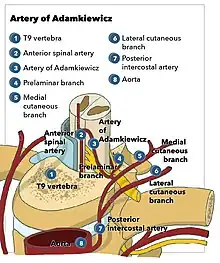

Aortic surgeries contribute to many iatrogenic spinal cord ischaemia, although its percentage is much lower than that of spontaneous type.[4] Thoracic endovascular aortic repair (TEVAR) was carried out to introduce a stent graft in order to treat thoracoabdominal aortic aneurysm, a condition of enlarged aorta with weakened vascular wall, as well as traumas and atherosclerosis.[12] Segmental medullary arteries, notably the artery of Adamkiewicz, could be excluded from circulation after blockage of intercostal arteries by the device, which directly branches from descending aorta.[12] Furthermore, during open repair, blood flow within aorta is halted by clamping to facilitate the sewing of interposition graft.[12] The reduced blood flow to anterior and posterior radicular artery could trigger spinal stroke.[12] Cases of spinal stroke following operations like aortography, spinal anesthesia and lumbar spine surgery are reported.[4]